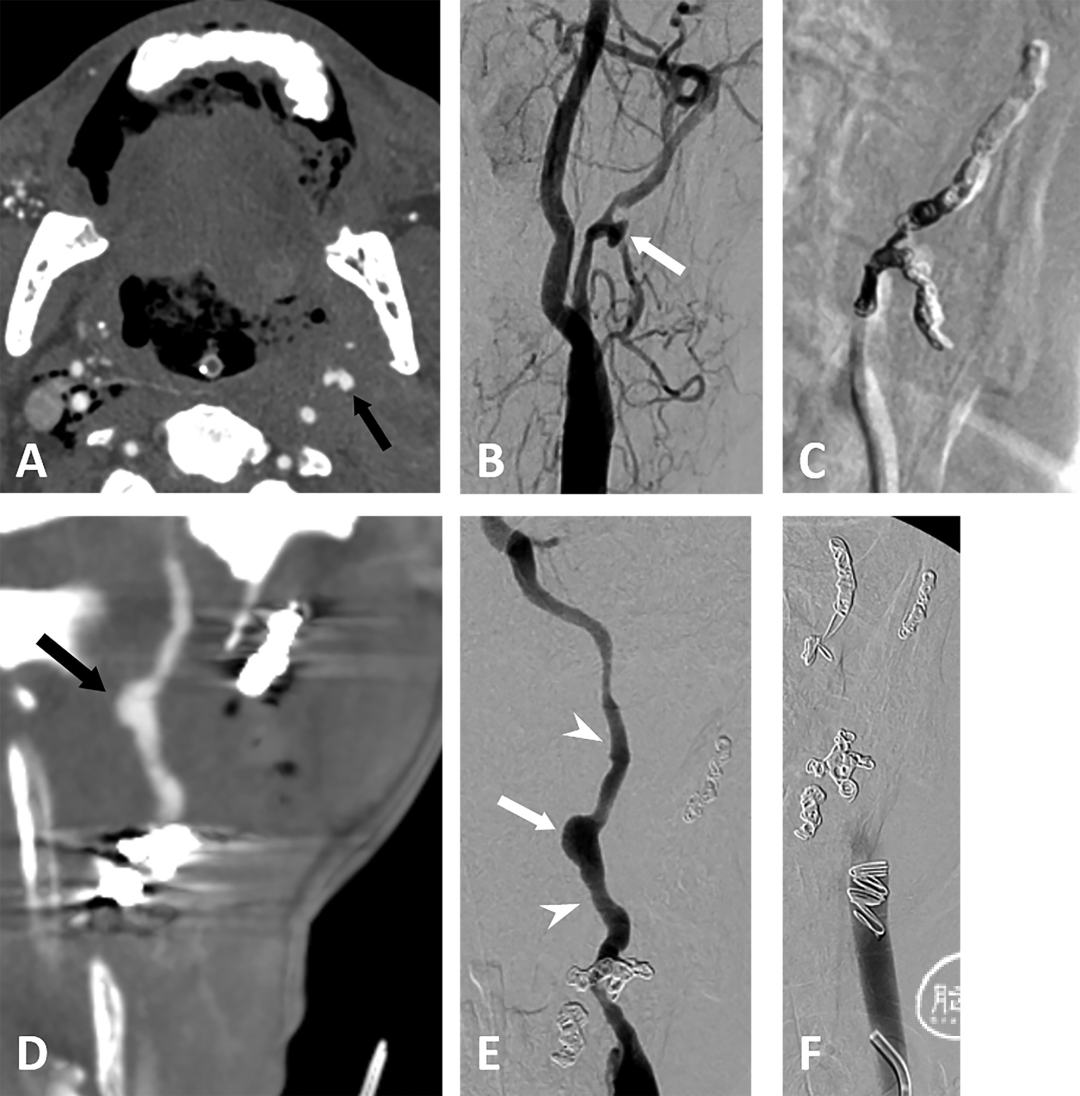

示例一. A,一名67岁左侧扁桃体癌男性患者,突发大量呕血。CTA显示肿瘤包绕左侧颈段颈内动脉及颈外动脉,并在颈外动脉处形成假性动脉瘤(箭头所示)。B,血管造影显示左颈外动脉近舌动脉开口处假性动脉瘤,无活动性造影剂外渗(箭头所示)。C,左颈外动脉圈陷术后状态(采用可推入弹簧圈,trapping with pushable coils)。D,左颈外动脉圈陷术4个月后再次发生呕血。CTA显示肿瘤体积增大,并在左颈段颈内动脉处形成新发假性动脉瘤(箭头所示)。E,血管造影显示左颈段颈内动脉假性动脉瘤(箭头),伴颈内动脉管壁不规整(箭号)。F,左颈总动脉及颈内动脉圈陷术后状态(采用可推入弹簧圈):